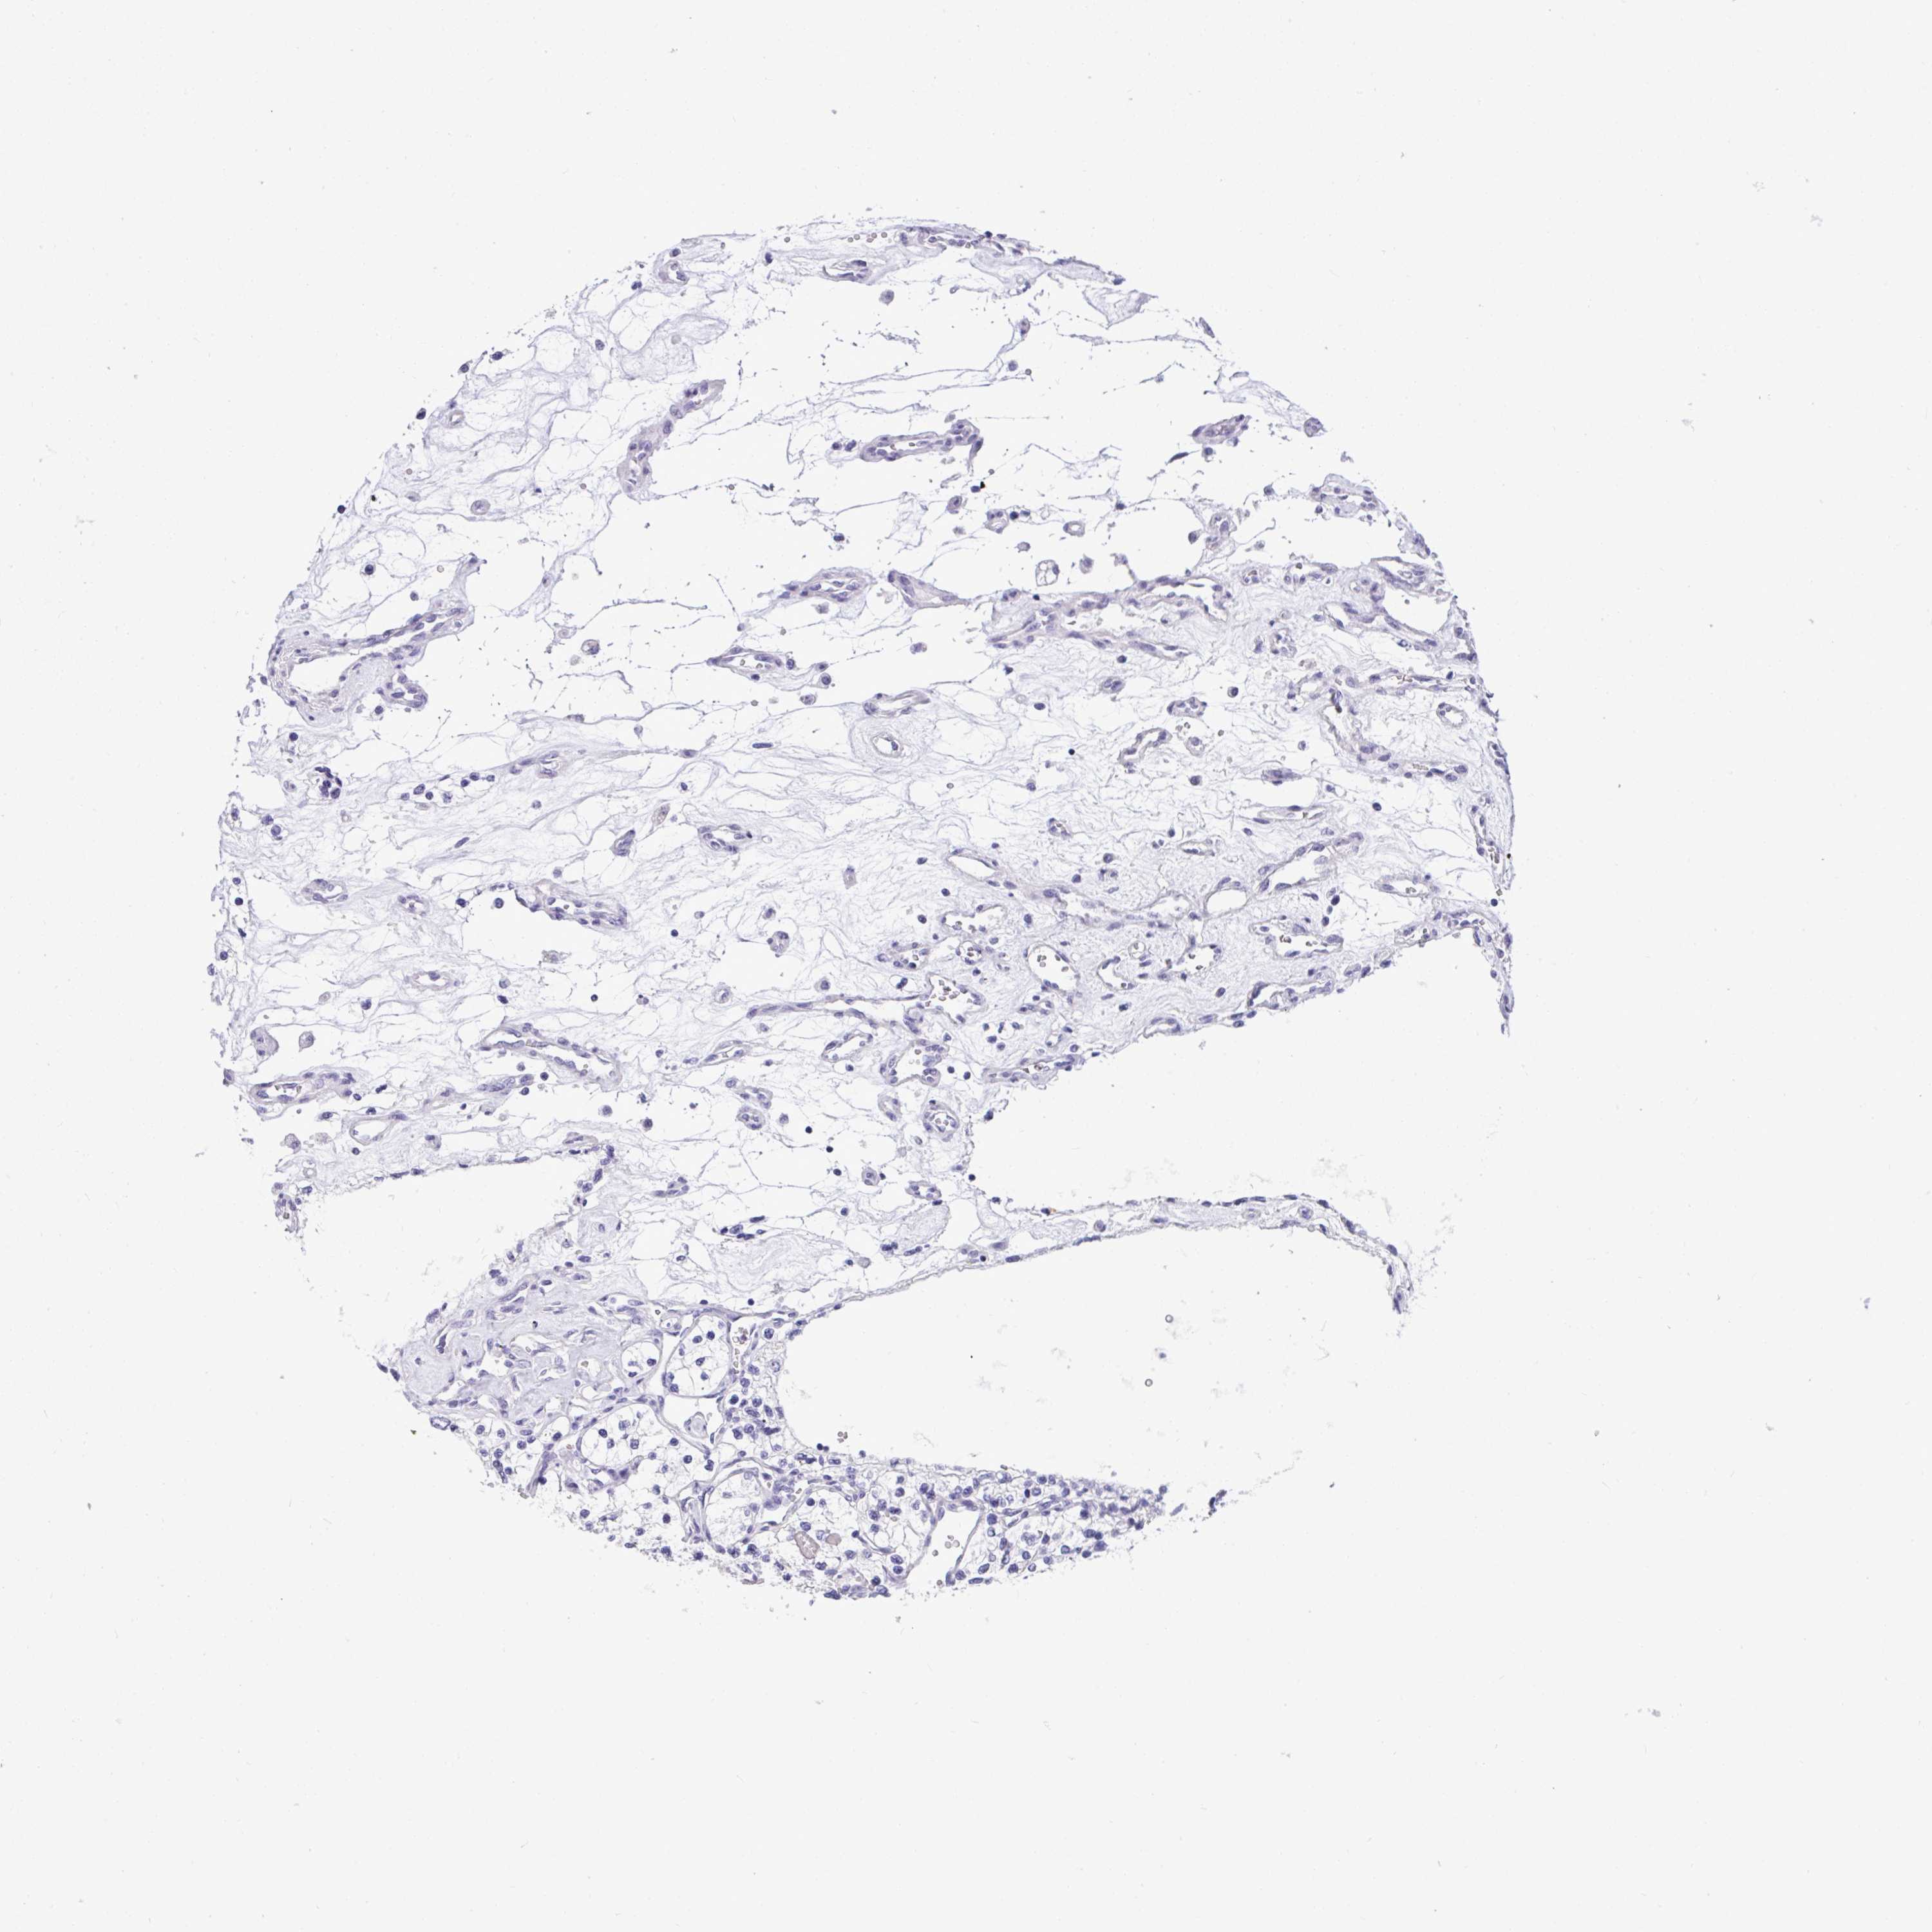

KIDNEY RENAL PAPILLARY CELL CARCINOMA (TCGA) - Interactive survival scatter ploti

The Survival Scatter plot shows the clinical status (i.e. dead or alive) for all individuals in the patient cohort, based on the same data that underlies the corresponding Kaplan-Meier plots. Patients that are alive at last time for follow-up are shown in blue and patients who have died during the study are shown in red.

The x-axis shows the expression levels (FPKM) of the investigated gene in the tumor tissue at the time of diagnosis. The y-axis shows the follow-up time after diagnosis (years). Both axes are complimented with kernel density curves demonstrating the data density over the axes. The top density plot shows the expression levels (FPKM) distribution among dead (red) and alive patients (blue). The right density plot shows the data density of the survived years of dead patients with high and low expression levels respectively, stratified using the cutoff indicated by the vertical dashed line through the Survival Scatter plot. This cutoff is automatically defined based on the FPKM cutoff that minimizes the p-score. The cutoff can be changed by dragging the vertical line or by entering a cutoff value in the square labeled "Current cut-off".

Under the Survival Scatter plot the p-score landscape (black curve; left axis) is shown together with dead median separation (red curve; right axis). Dead median separation is the difference in median mRNA expression between patients who have died with high and low expression, respectively. It is calculated as follows: median FPKM expression of dead patients with high expression - median FPKM expression of dead patients with low expression. This is intended to aid the user in visually exploring custom cutoffs and the associated p-scores and dead median separation.

Individual patient data is displayed and can be filtered by clicking on one or more of the category buttons on the top of the page. Categories describing expression level and patient information include: high, low, alive, dead, female, male and tumor stages. The scale of the x-axis can be toggled between linear and log-scale by clicking on the "x log" button. Mouse-over function shows TCGA ID, patient information and mRNA expression (FPKM) for each patient.

& Survival analysisi

Kaplan-Meier plots summarize results from analysis of correlation between mRNA expression level and patient survival. Patients were divided based on level of expression into one of the two groups "low" (under cut off) or "high" (over cut off). X-axis shows time for survival (years) and y-axis shows the probability of survival, where 1.0 corresponds to 100 percent.

YBX2 is not prognostic in Kidney Renal Papillary Cell Carcinoma (TCGA)